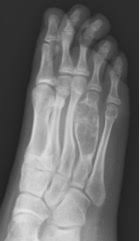

Bone Pain Causes Cancer Symptoms And Treatment from post.medicalnewstoday.com It can look like a: Foot or toe cancer (digital and soft tissue cancer), which can include squamous cell carcinoma, melanoma, osteosarcoma, mast cell tumor, and malignant soft tissue sarcoma is common in dogs. Squamous cell carcinoma is the most common form of cancer on the skin of the feet. Bone cancer begins in the bone instead of developing due to cancer cells spreading from other parts of the body. Sometimes, people with bone sarcoma do not have any of these changes. Your foot has typically thin soft tissue layer and gets continuous exposure to the outside environment. A benign bone tumor of the foot will manifest as a lump, with or without pain, whereas bone cancer is most often accompanied by pain at the location of the tumor. If the cancer develops in the legs, as it does in most cases, the usual course of treatment is amputation.

Aside from looking like a changing mole, a melanoma on the foot can appear as a: For instance, lung cancer that spreads to the bone is made of lung cancer cells. A type of bone cancer called osteosarcoma is the most common type of primary bone cancer in dogs, accounting for over 95% of all bone tumors. Early on, the pain may only occur at night, or when you are active. The scc does not retain its appearance as a solid mass. Jaw cancer results in pain in the area with difficulty in opening the mouth. Bone pain can cause a dull or deep ache in a bone or bone region (e.g., back, pelvis, legs, ribs, arms). Foot or toe cancer (digital and soft tissue cancer), which can include squamous cell carcinoma, melanoma, osteosarcoma, mast cell tumor, and malignant soft tissue sarcoma is common in dogs. People with bone sarcoma may experience the following symptoms or signs. However, you should still check your symptoms and talk to your doctor, as symptoms like bone pain, fractures, swelling, and fatigue can indicate cancer or another issue that needs to be treated. In fact, noncancerous bone tumors are much more common than cancerous ones. Malignant cells in the jaw tend to spread quickly to adjacent organs. Bone cancer is a fairly rare disease, so if you've developed bone pain, don't jump to conclusions.

The bone may look ragged, or it may appear to have a hole in it. Aside from looking like a changing mole, a melanoma on the foot can appear as a: Leg pain due to bone cancer may worsen during nighttime. Sometimes, people with bone sarcoma do not have any of these changes. A benign bone tumor of the foot will manifest as a lump, with or without pain, whereas bone cancer is most often accompanied by pain at the location of the tumor.

Life At Dearborn Congregational Lung Cancer Bone Cancer And Neuropathy Oh My from 64.media.tumblr.com Cancer that arises from the jaw bone is termed primary jaw cancer. Lumps, swellings, fractures, joint tenderness and pain are some common symptoms of bone cancer in ankle and foot. Aside from looking like a changing mole, a melanoma on the foot can appear as a: Sometimes, people with bone sarcoma do not have any of these changes. Bone cancer can weaken the bone it's in, but most of the time the bones do not fracture (break). It is important that all these symptoms are identified at an early stage so, to. For instance, lung cancer that spreads to the bone is made of lung cancer cells. This article will look at what bone metastasis is and its treatment options.

When a bone tumor grows, it presses on healthy bone tissue and can destroy it, which causes the following symptoms: Bone cancer can begin in any bone in the body, but it most commonly affects the pelvis or the long bones in the arms and legs. However, malignant cells can also spread to the jaw from other cancers in the neck and head, termed as secondary jaw cancer. Bone cancer is a fairly rare disease, so if you've developed bone pain, don't jump to conclusions. It may resemble a plantar's wart or a foot ulcer, and it may feel scaly. Rarely, the affected bone may weaken and break on its own. A tumor that has metastasized to bone is not made of bone cells. Leg pain due to bone cancer may worsen during nighttime. Primary bone tumors can be either benign or malignant. They work to destroy the tumor or slow down the growth of cancer cells. Aside from looking like a changing mole, a melanoma on the foot can appear as a: If the cancer develops in the legs, as it does in most cases, the usual course of treatment is amputation. However, you should still check your symptoms and talk to your doctor, as symptoms like bone pain, fractures, swelling, and fatigue can indicate cancer or another issue that needs to be treated.

Other types of bone cancer include chondrosarcoma, fibrosarcoma, and hemangiosarcoma. Bone cancer is a fairly rare disease, so if you've developed bone pain, don't jump to conclusions. Primary bone tumors are relatively rare after the fourth decade of life and less frequent as compared to secondary bone tumors. When a bone tumor grows, it presses on healthy bone tissue and can destroy it, which causes the following symptoms: There are different types of primary bone cancers, like osteosarcoma and ewing sarcoma. Malignant cells in the jaw tend to spread quickly to adjacent organs. Jaw cancer results in pain in the area with difficulty in opening the mouth. What bone metastasis looks like. Cancer in the bones of the spine can press on nerves, causing numbness and tingling or even. People with a fracture next to or through a bone tumor usually describe sudden severe pain in a bone that had been sore for a few months. For instance, lung cancer that spreads to the bone is made of lung cancer cells. If the cancer develops in the legs, as it does in most cases, the usual course of treatment is amputation. Bone tumors of the foot are rare, comprising only three to six percent of all bone tumors, and are benign in 75 to 85 percent of cases (sarcoma, 2013).